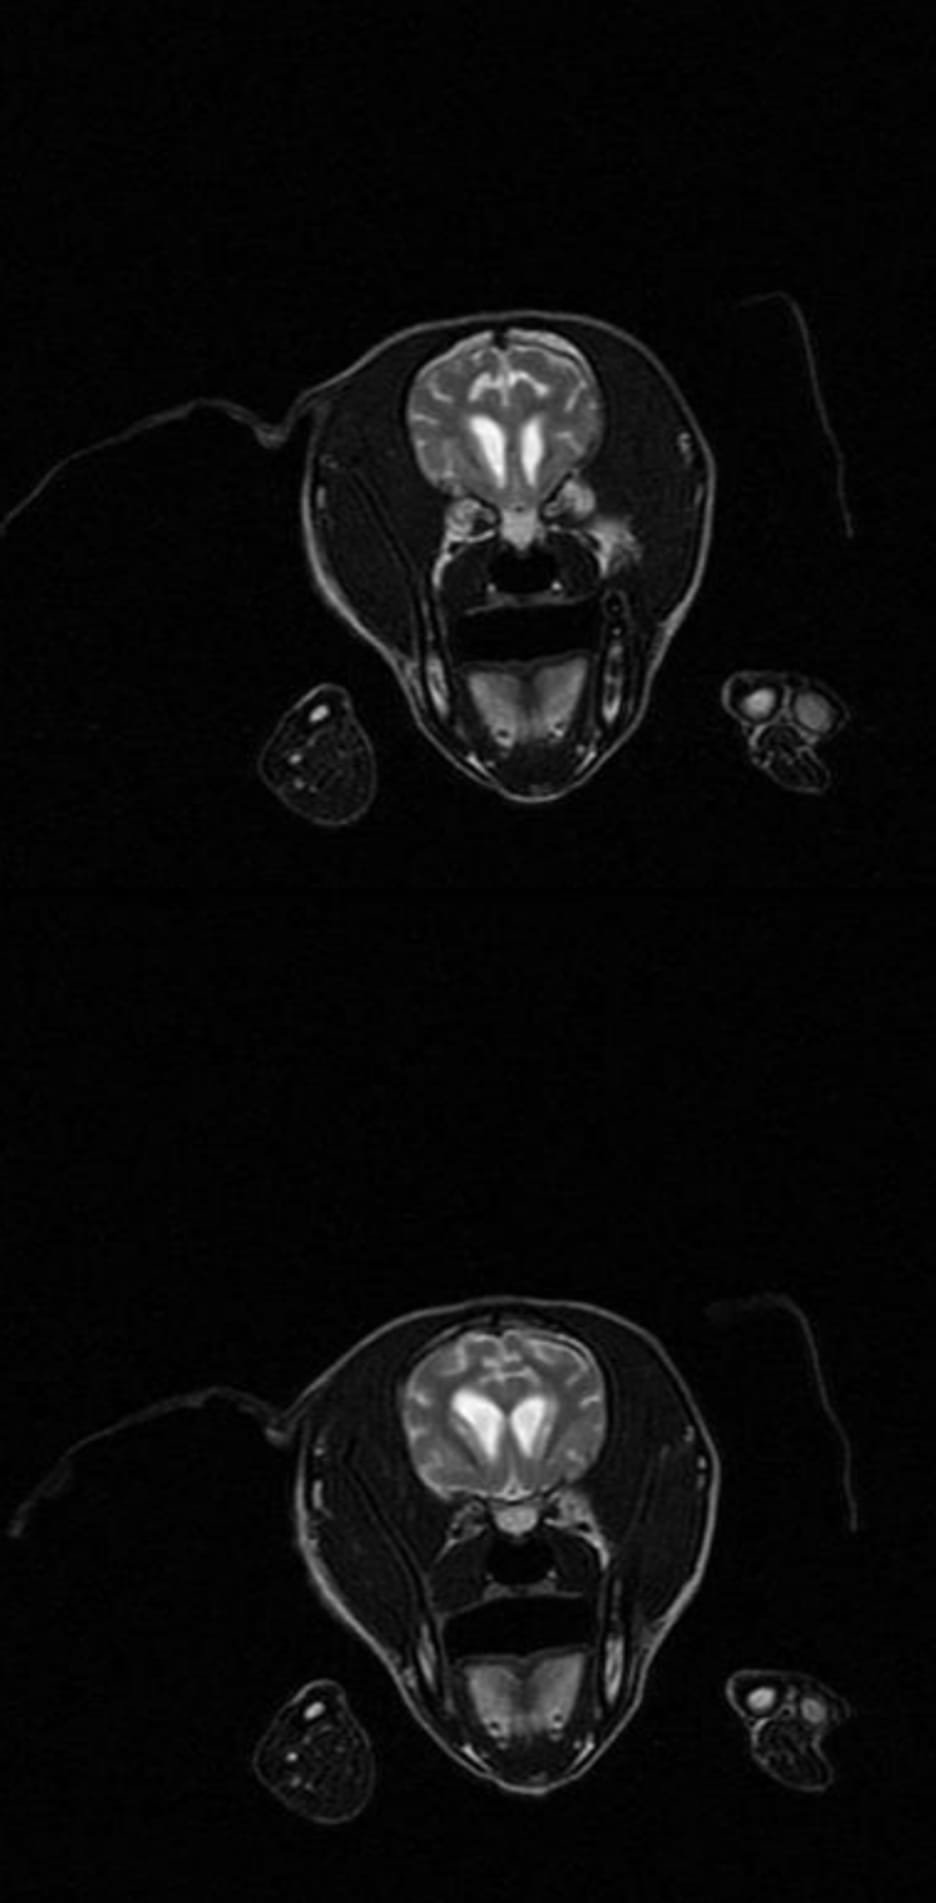

Die Untersuchung von Nike konnten wir dank der vielen Spenden jetzt auf den Weg bringen. Ein Ergebnis vom MRT des Kopfes haben wir leider noch nicht, aber so können wir prüfen, ob ein Defekt im Gehirn vorliegt, was ihre Sehfähigkeit beeinträchtigt. Sie schien am Anfang ganz blind, das ist sie aber eindeutig nicht, sie hat sich bisher richtig gut gemacht und hoffen wir, dass wir mit dem Ergebnis einen Ansatz zur Heilung haben, die süße Maus hat es verdient! 🍀

Die Ergebnisse von Nikes MRT sind da! Die genaue Untersuchung des Kopfes hat gezeigt, dass sie mit etwas Zeitverzögerung aufgrund eines angeboren Gendefekts erwachsen wird, aber keine weiteren Gesundheitsprobleme oder Beeinträchtigungen zu erwarten sind. Gott sei Dank. Die partielle Blindheit in einem Auge wird weiter abnehmen, Nike wird ein ganz normales Leben führen können, wir freuen uns sehr!